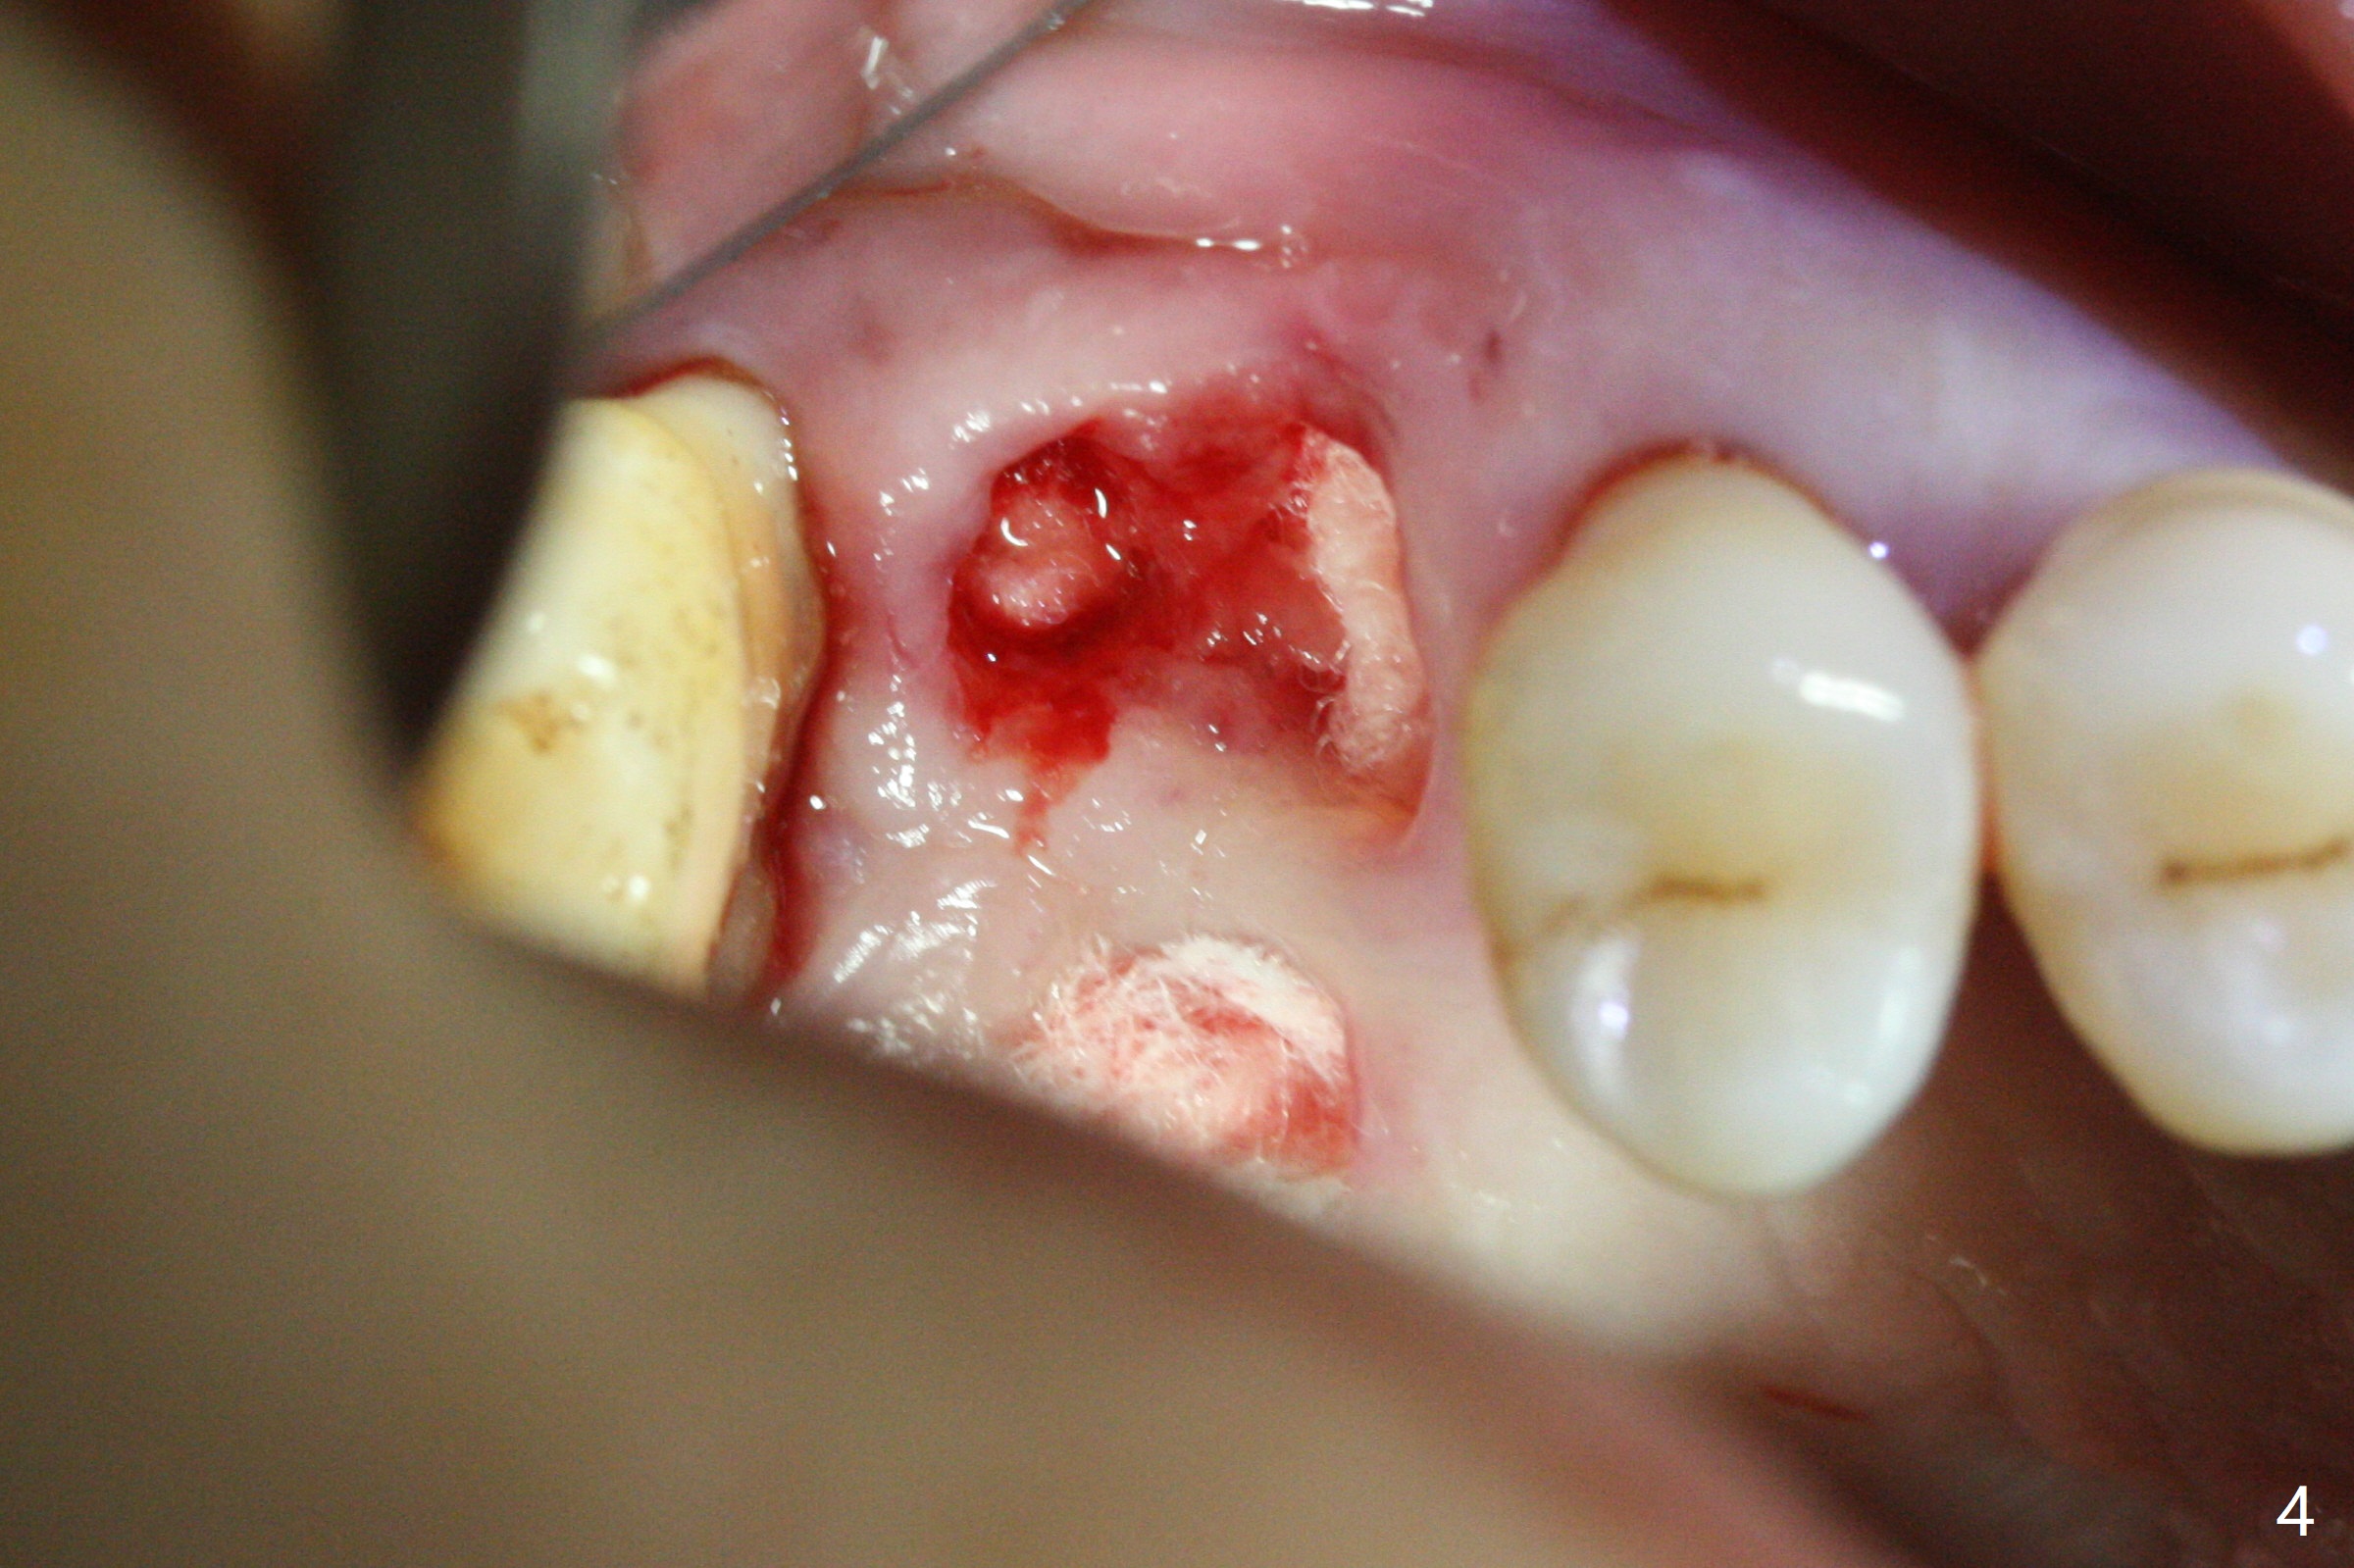

The tooth #3 has gingival recession moderate buccally (Fig.1) and severe palatally (Fig.2 P). The remaining bone height is estimated 4 mm (Fig.3). After extraction and debridement, the 3 sockets are packed with 2% Lidocaine 1:50,000 Epinephrine saturated gauze (Fig.4). When the gauze is removed from the buccal sockets (Fig.5 black area), the buccal portion (B) of the septal gingiva (*) is sectioned from the buccal gingiva (Fig.6 curved white line) and elevated from the underlying septal bone and pushed palatally (arrow). The septal gingiva (including the buccal portion) will be the palatal soft tissue wall of the subsequent osteotomy, providing blood supply to allograft to be placed. In short, the septum (through the buccal socket) will be the osteotomy site.

Initial osteotomy depth is 4 mm (Fig.7). The sinus membrane is found to be perforated when the depth increases to 8 mm. The latter could be prevented by taking CT and/or using osteotome. The subsequent osteotomy depth is 5 mm until 4.0 mm in diameter. When the 4.5 mm tap is inserted with initial stability, the shortest implant (8.5 mm, Fig.8 green) will be partially protruded into the sinus and partially exposed in the socket and the cuff of the abutment is expected to be around 6 mm (pink). Since the 5 mm tap achieves primary stability, a 5x8.5 mm implant (following placement of Osteogen plug to repair the perforated sinus membrane) is placed at the level just mentioned (Fig.9). Vanilla Graft mixed with minimal autogenous bone is packed (Fig.10.11 *) before and after insertion of a 6.5x5(4) mm abutment. An immediate provisional as well as a piece of Osteogen plug is fabricated to close the socket gap. The provisional and the abutment are dislodged 1 month postop (Fig.12). The wound has healed. The abutment is reloaded without the provisional. The implant appears to osteointegrate 4.5 months postop (Fig.13); in addition the bone graft seems to have migrated toward the roots of the neighboring teeth (arrows).